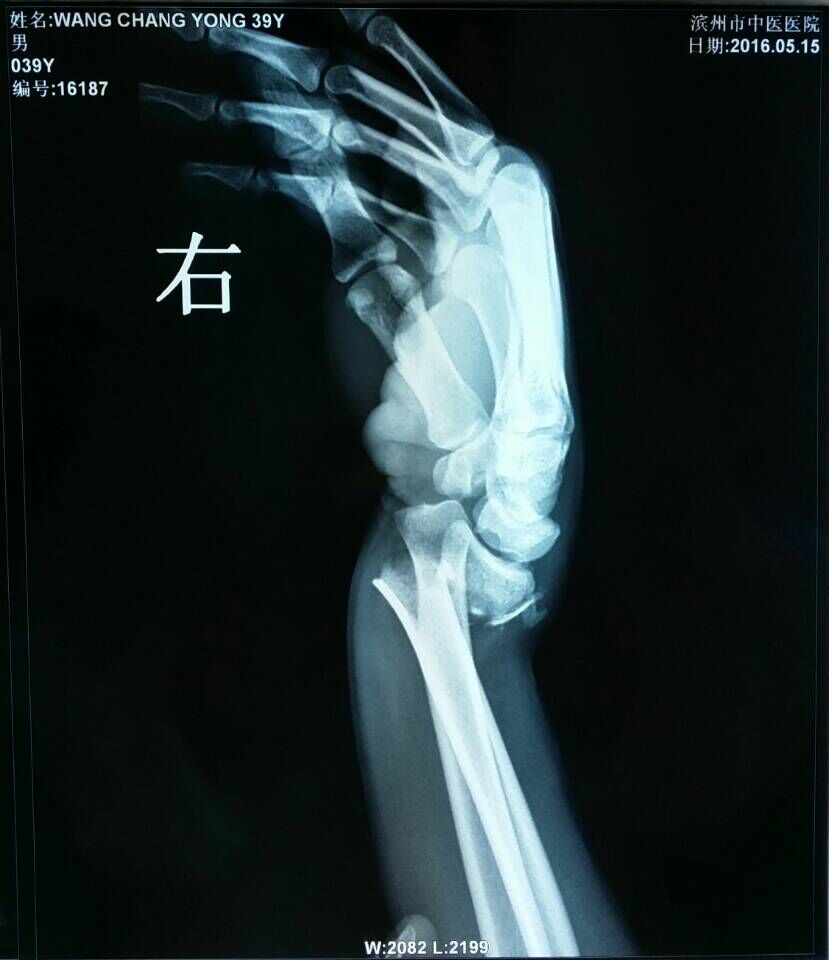

患者王某,男,39岁,踢足球时摔伤右腕关节,右腕部肿胀疼痛、活动受限2小时来我院骨伤科就诊。骨伤科刘陆勇大夫及时安排患者进行X片拍照,X-ray片(图1,2)示:右桡骨远端骨折,远端向桡侧、背侧移位,近端向掌侧移位,右端尺骨茎突骨皮质不连续,见游离骨片影,初步诊断为“桡骨远端骨折”。在确定骨折损伤程度后,刘陆勇大夫和杨晓晓大夫采用中医传统整复手法,给予患者行手法整复石膏外固定,整复后患者再次行x-ray检查(图3,4),x线片显示复位情况良好,效果显著。此次治疗使患者避免切开手术及二次手术取内固定的痛苦,最大限度地减轻了病人的经济负担,受到了病人的一致好评。